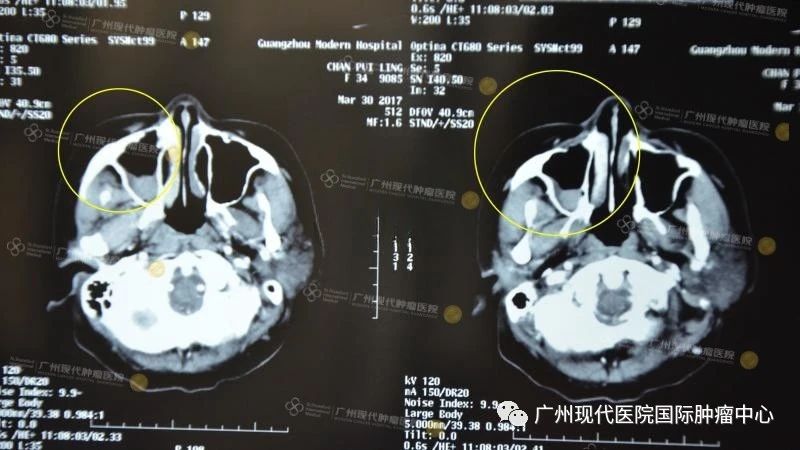

(2017年2月治療前)

(鼻竇腔內(nèi)被瘤物質(zhì)充滿,眼球被擠壓移位)

2017年,33歲的陳女士孤身一人來(lái)到我院。經(jīng)過(guò)細(xì)致檢查,醫(yī)院MDT團(tuán)隊(duì)為陳女士制定了“介入療法+粒子植入療法”的綜合微創(chuàng)治療方案。治療前,為減輕陳女士的擔(dān)憂,主治醫(yī)生向陳女士作了詳盡的說(shuō)明:介入治療就是利用特制導(dǎo)絲等精密器械,將抗腫瘤藥物注入腫瘤內(nèi)部,同時(shí)對(duì)腫瘤的供血?jiǎng)用}進(jìn)行栓塞,從而實(shí)現(xiàn)腫瘤縮小甚至消失的目的,具備創(chuàng)傷小、副作用少、恢復(fù)快等優(yōu)點(diǎn)。而粒子植入則是將125碘粒子植入腫瘤內(nèi)或受腫瘤浸潤(rùn)的組織中,通過(guò)粒子釋放出的γ射線,對(duì)腫瘤起到內(nèi)放射治療作用,可以很好地治療轉(zhuǎn)移性腫瘤病灶。第一次介入治療后,短短3天時(shí)間,陳女士右眼下的腫瘤便有了明顯縮小,第四次治療之后,臉部基本就看不出異常了。

(鼻竇腔內(nèi)瘤物質(zhì)減少,空腔基本恢復(fù)正常,眼球恢復(fù)正常)

(治療前VS第一次治療后)